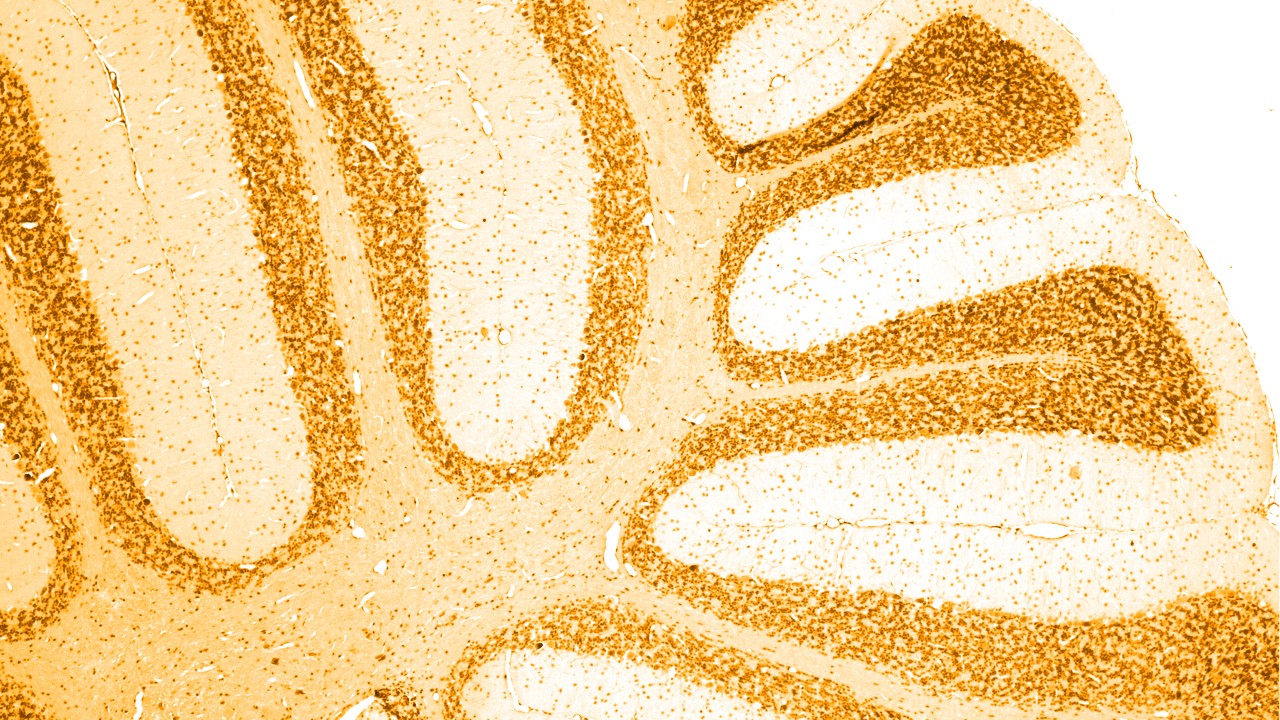

Neurological disorders are diseases of the central and peripheral nervous systems. In other words, the brain, spinal cord, nerves and muscles, which regulate and coordinate body’s activities.

Dementia is a progressive degeneration of the brain and its ability to function. It is an extremely serious condition that changes a person’s personality and affects their ability to go about their daily life. Dementia mostly occurs in the elderly.

There are a number of different causes of dementia, of which the most common is Alzheimer’s disease, linked with the build-up of abnormal ‘amyloid plaques’ and ‘tau tangles’ in the brain. Certain other types of dementia also have an abnormal build-up of tau protein in the brain; as a group, these are termed ‘tauopathies’.